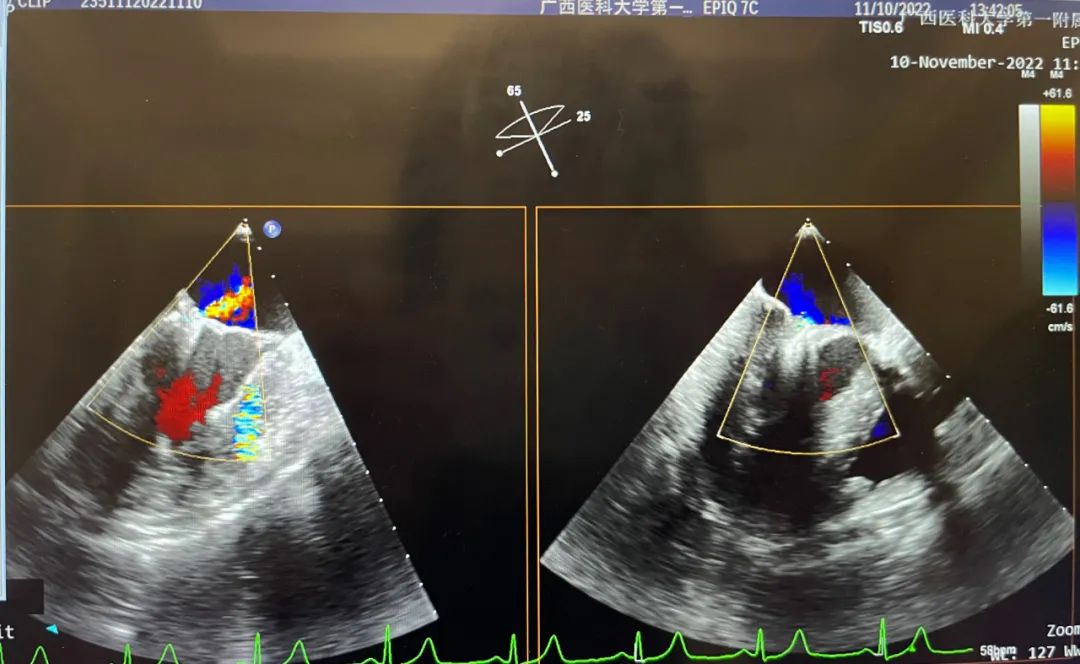

术后

术后实时超声显示二尖瓣反流明显改善,术前反流4+,术后小于1+,跨瓣平均压差1mmHg,左上和右上肺静脉逆流明显改善,血压升高恢复正常,其他各项生理指标正常,手术顺利完成。